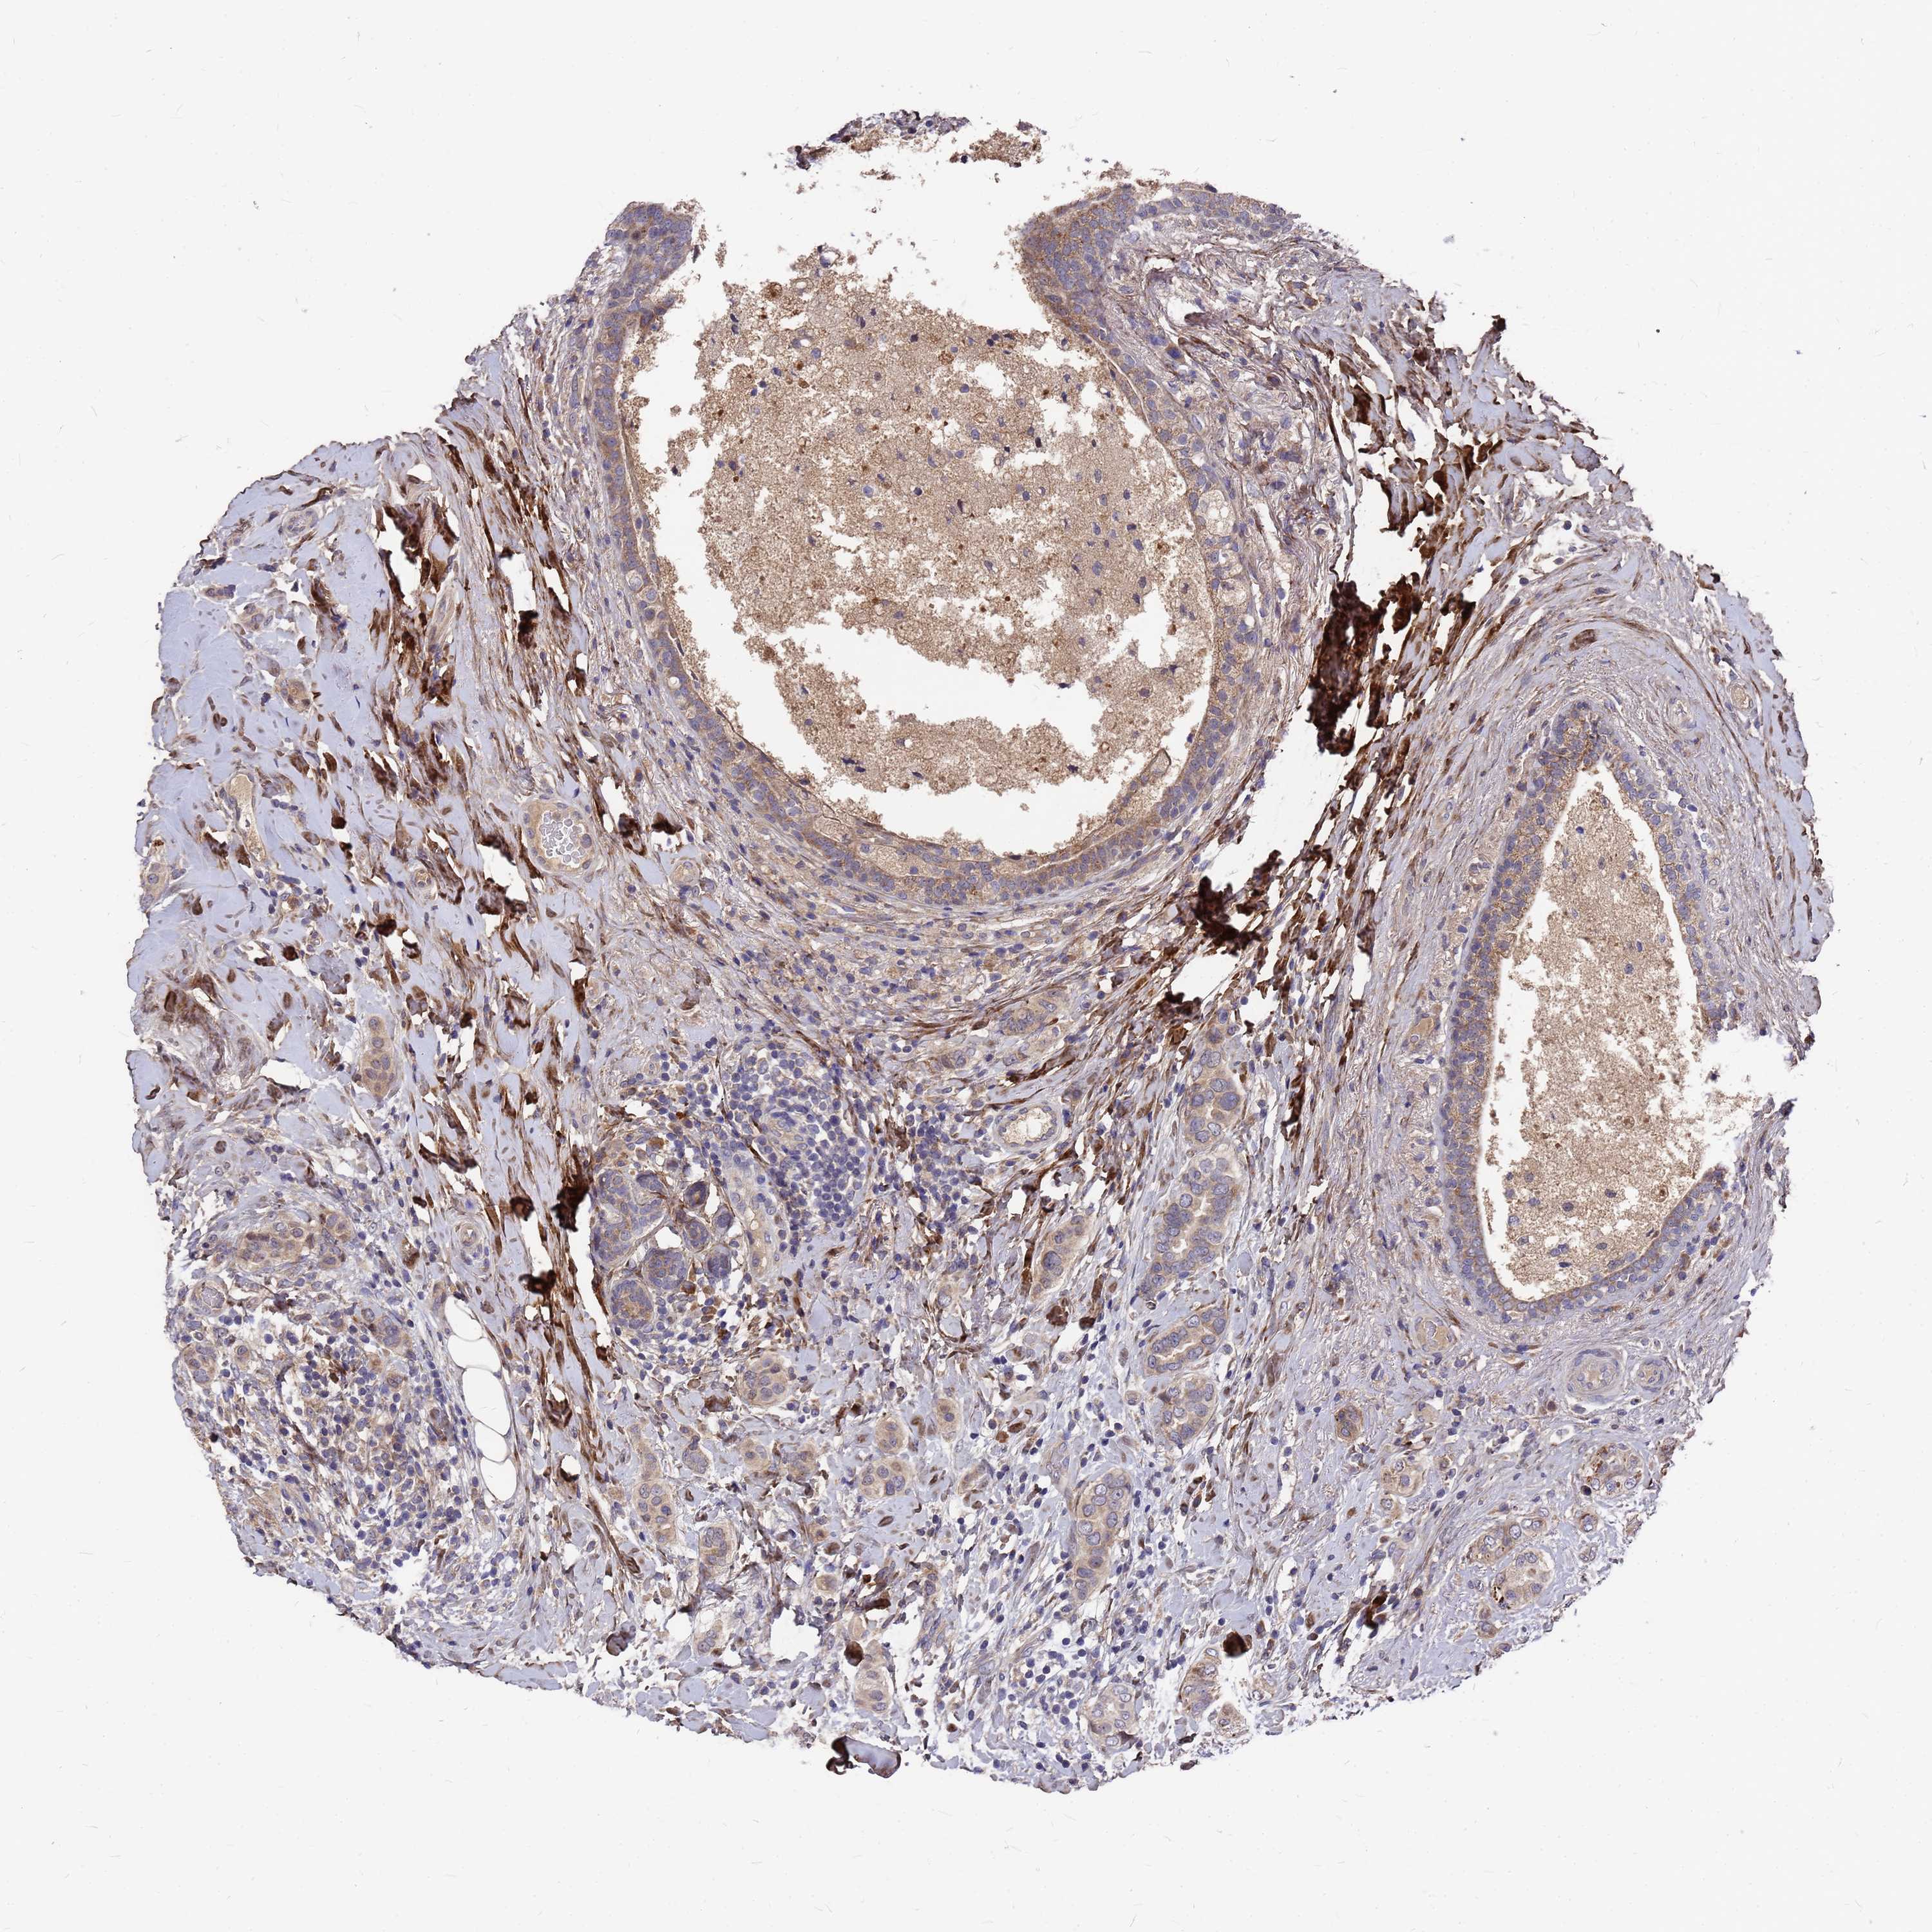

CANCER BREAST CANCER Show tissue menu

BRCA TCGA BRCA VALIDATION PROTEIN EXPRESSION